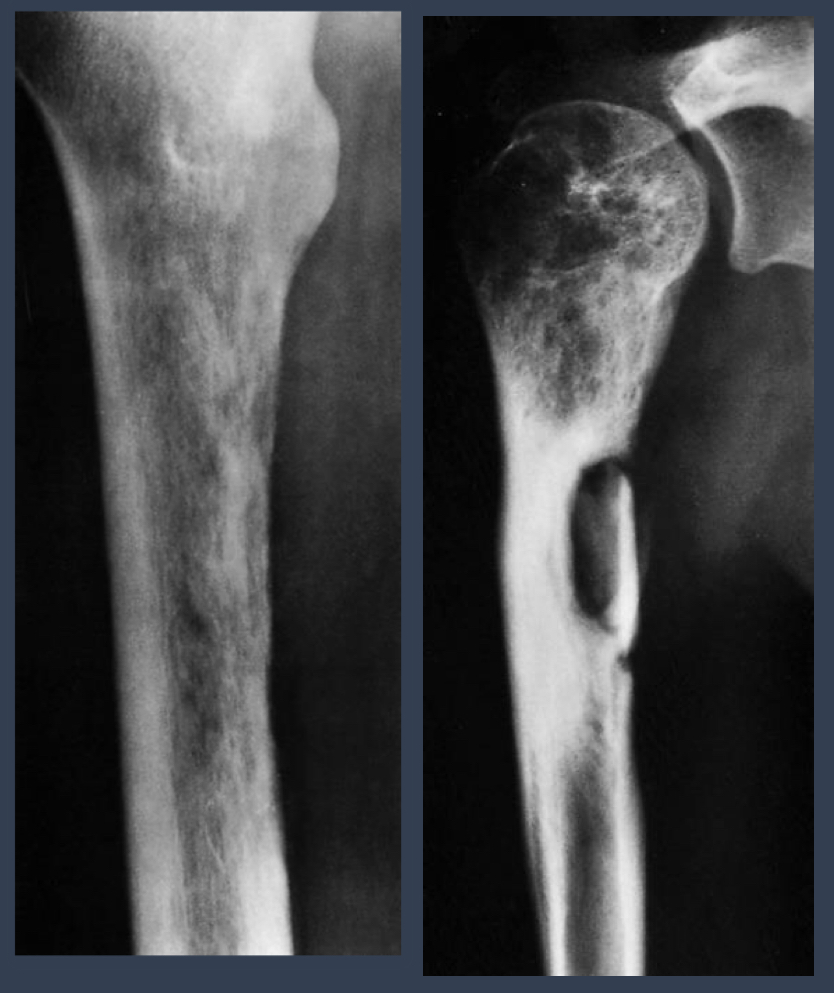

photo: same patient, repeat xrays

what are these called?

what condition is this?

osteomyelitis

what is the left? what is the right

left: acute osteomyelitis

right: chronic osteomyelitis

what is this?

brodie abscess